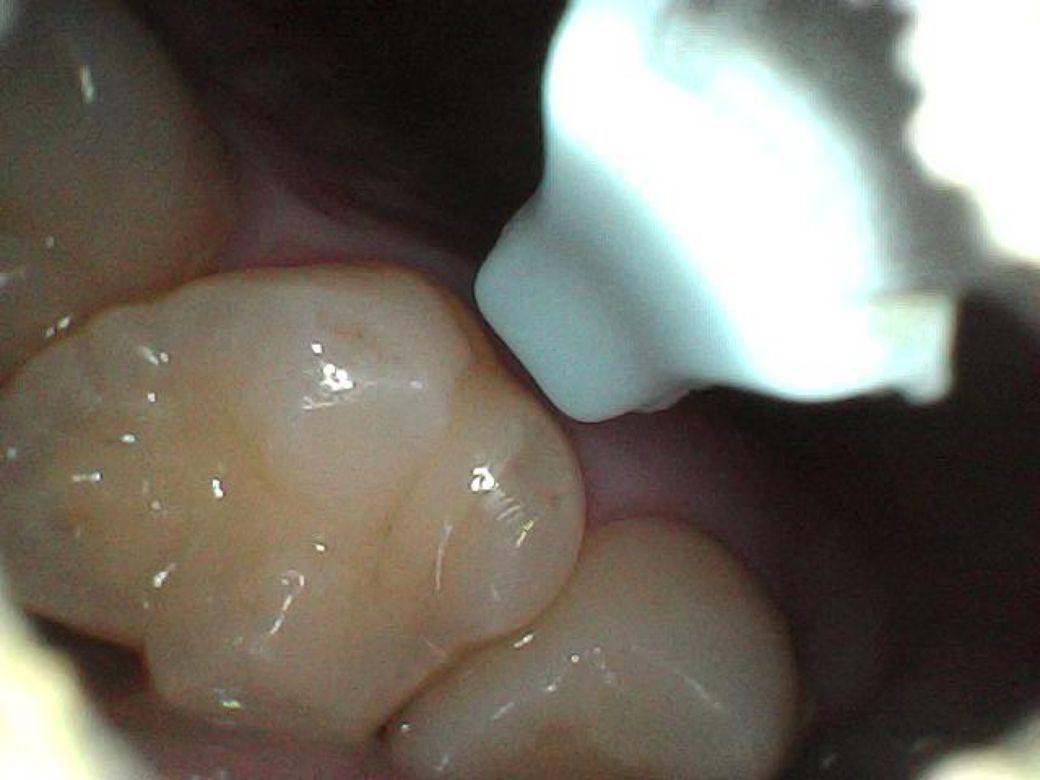

• 1번 째 사진

아침에 일어나 양치를 하고 혀로 이빨을 훑어보다 오른쪽 윗니 중간, 왼쪽 윗니 중간에 하나씩 뭐가 만져지더라구요

예전엔 매끈했던 부위인데, 지금은 뮌가 까끌까끌해요

내시경 귀이개로 들여다봐도 뭔지 모르겠네요